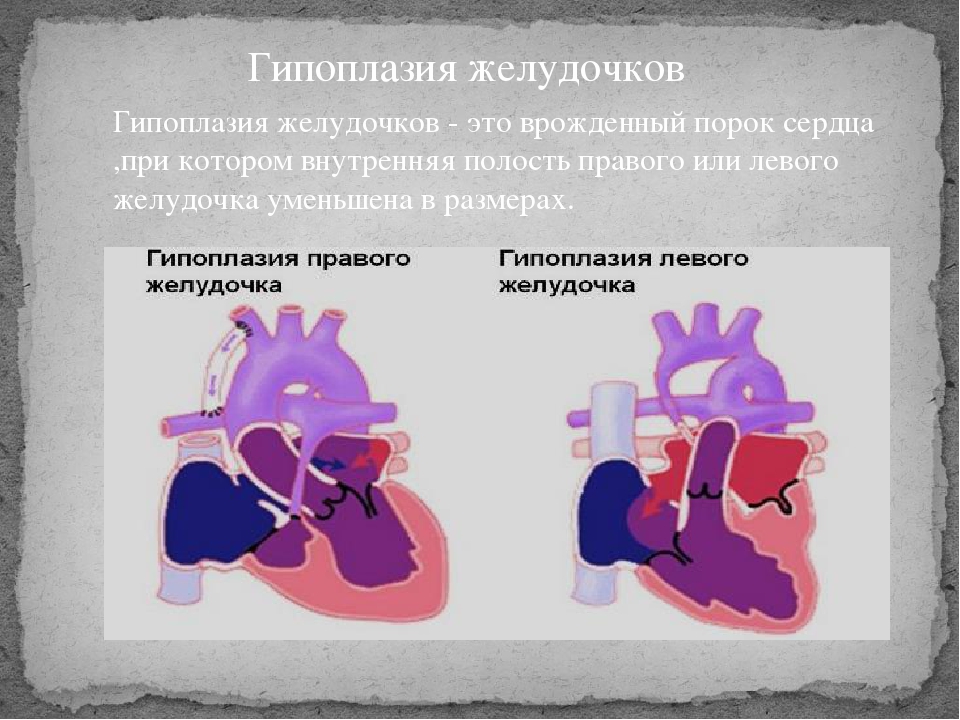

Пороки сердечно-сосудистой системы: виды и признаки